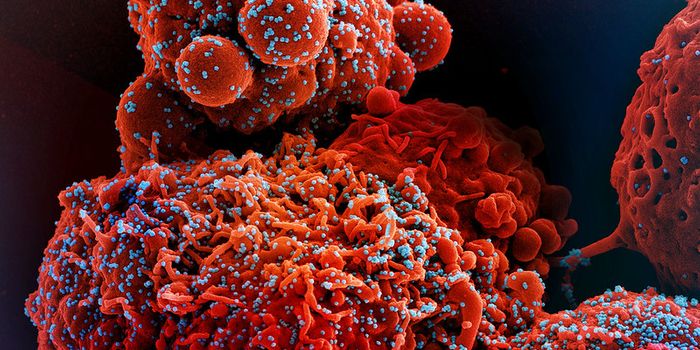

DEC 21, 2023Drug Discovery & DevelopmentEpigenetic mechanisms responsible for iinitiating HIV latency and creating a long-lived viral reservoirs